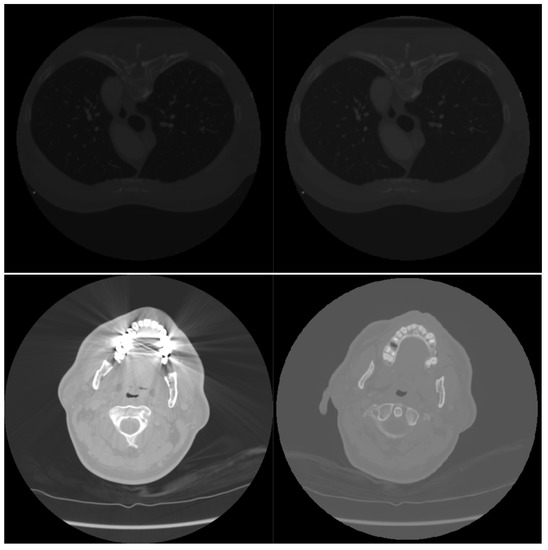

where g is the equalized sub-part of the image, is the normalized histogram and L is the maximum intensity of a pixel. Some slices normalized by AHE are reported in Figure 2.

Figure 2.

A low-light scan (upper left image); a scan that contains some light peaks (bottom left image). AHE-normalized versions of the scans are shown on the right.